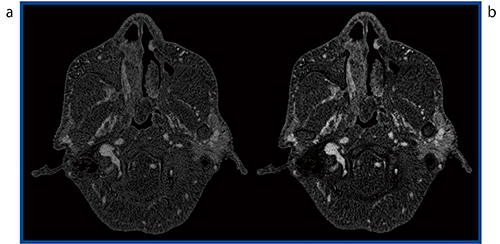

症例7は,75歳,男性の鼻腔腫瘍であるが(図7),腫瘍の造影効果が高くないためにSURESubtractionを用いても,腫瘍範囲の同定が困難である(図7 a)。そこで,造影効果を増強させる“CE Boost”を併用してSURESubtractionを行うと,コントラスト向上によりサブトラクション画像が明瞭化し,造影範囲の同定が容易になった(図7 b)。

図7 症例7:鼻腔腫瘍

a:SURESubtraction b:SURESubtraction+CE Boost